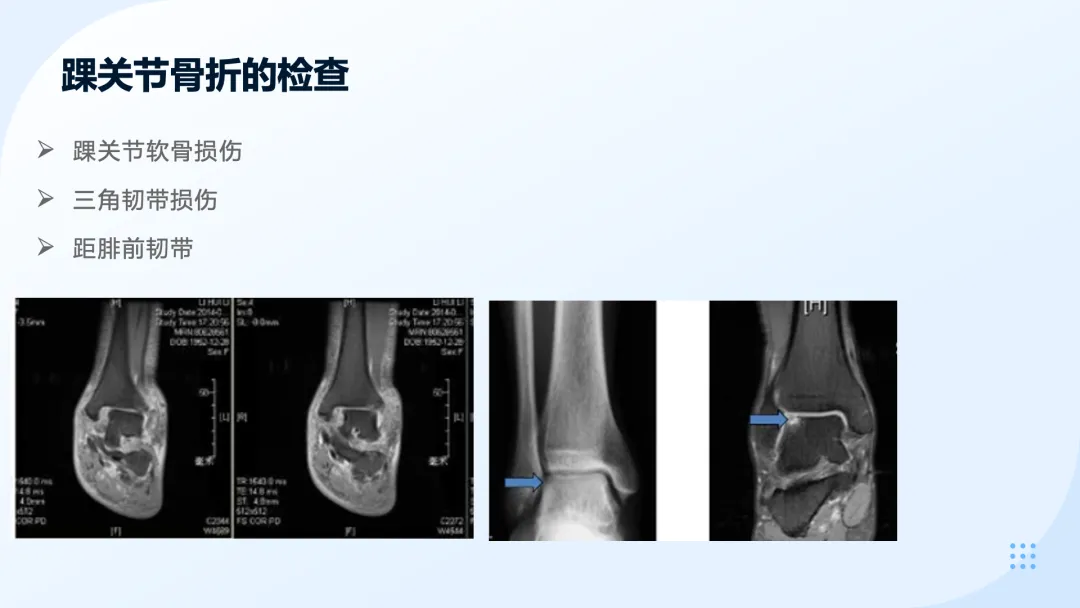

>医护PPT课件:踝关节骨折围手术期护理